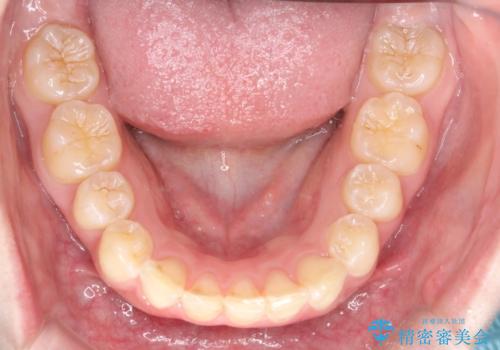

- 前歯のガタガタが気になるとのことで来院されました。

上顎の前歯の叢生があったのと、下あごの前歯が通常より1本欠損(先天欠損)していました。

上顎の歯と歯の間をわずかに削りスペースをつくり、並べる計画としました。インビザライン治療を選択されました。

しっかりとインビザラインを使用していただけたので、スムーズに治療を終了させることができました。